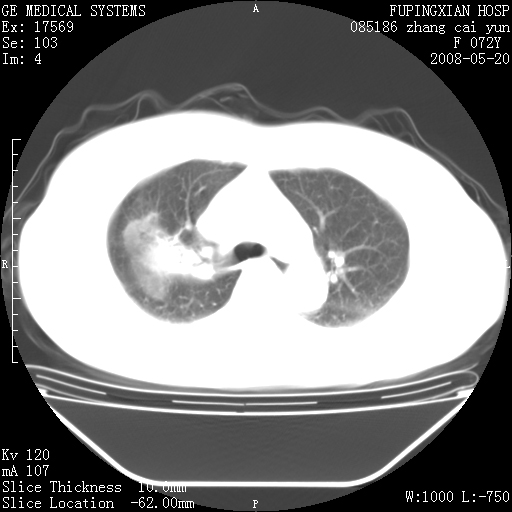

标题: CT13542:发热,咳嗽数日,经抗菌素治疗好转,请大家看排除 [打印本页]

标题: CT13542:发热,咳嗽数日,经抗菌素治疗好转,请大家看排除

上叶支气管略变窄并通畅,内壁光滑。考虑:单纯阻塞性肺炎!

有节段性阻塞性肺炎与不张,近段支气管狭窄,周围散在肿大淋巴结影,以周围型肺癌可能性大,建议纤支镜检查。

右肺上叶实变影,内见支气管充气征,右上叶支气管通畅,肺门区未见软组织密度影,抗炎治疗有效,考虑炎症,建议继续抗炎治疗复查。

右肺阻塞性肺炎  不除外支气管内膜结核

考虑为:右肺上叶感染性病变。建议:1)继续抗炎治疗后复查。2)必要时行纤支镜检查。